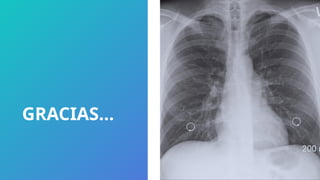

MANIFESTACIONES

RADIOLOGICAS

 Radiografía PA de Tórax de un derrame pleural masivo con desplazamiento del mediastinico (A), y

sin desplazamiento (B), obsérvese el luminograma